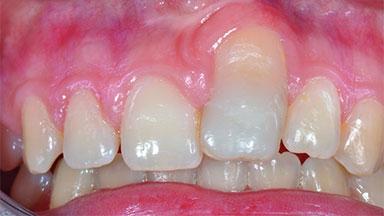

Replacement of an Ankylosed Central Incisor with a Gingival Recession: Tooth Extraction with Socket Grafting and Late Implant Placement with Simultaneous Contour Augmentation

In 2008, a healthy 15-year-old female, non-smoking patient presented at our clinic with a major esthetic problem of tooth 21. Her dental history revealed that the tooth had been avulsed by trauma years before. As a result, the replanted and temporarily splinted tooth had ankylosed and was in severe apical malposition. The ankylosed tooth exhibited a significant gingival recession that disturbed the patient greatly. Due to the patient’s low age and with her skeletal growth not completed, periodic follow-up visits were scheduled to monitor the situation until the patient was old enough for implant therapy.

Abutment Type CAD/CAM

Prosthesis Type FDP